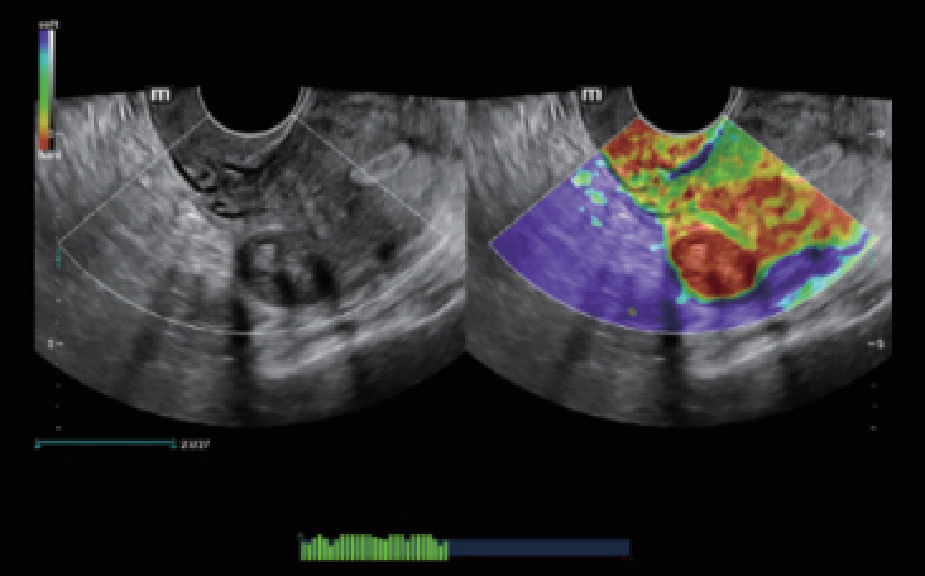

ZST +? ???? ?? ???? ???

ZST+ ???? ???? ??? ???? ??? ?????. ??? ????? ??? ? ???? ?? ??? ?? ????? ?????. ?? ???, ?? ???, ?? ??? ?? ?? ?? ??? ??? ???? ???? ??? ?? ??? ?? ???? ?? ??? ?? ??? ?????.